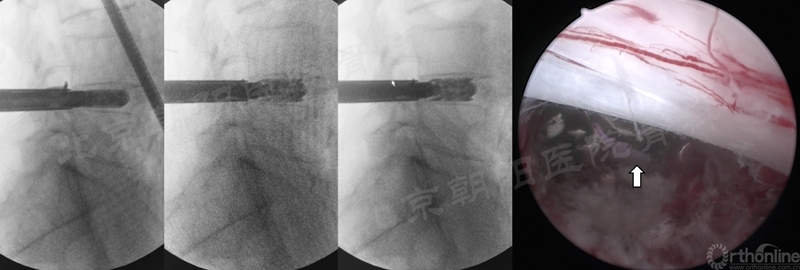

1、 镜下迷失——减压部位错误

#1例UBE,术前计划减压范围如绿色部分,术中减压操作集中在了硬膜背侧,甚至多数时候在对侧操作,实际减压部位在红色部分,使椎管减压的效果不理想。

3、 硬膜损伤

#2例UBE,游离型LDH,未做好充分的上关节突内侧减压,误把硬膜当做突出的间盘,导致硬膜撕裂。及时转切开减压,取出大块髓核组织。